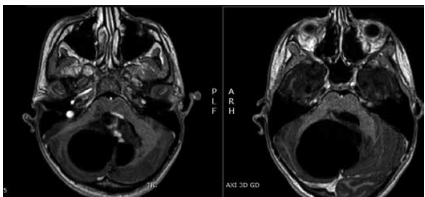

Um jovem de 14 anos de idade deu entrada no pronto-socorro com queixa de cefaleia persistente. A anamnese evidenciou que a cefaleia era matinal, com dois meses de evolução e obtinha alívio após vômitos. O paciente apresentou dificuldades de equilíbrio e de coordenação motora. Ele estava consciente, orientada, com marcha atáxica. O paciente apresentava incoordenação do membro superior ao realizar a prova índice-nariz. Foi realizada a ressonância do encéfalo com contraste, conforme ilustra a imagem a seguir.

Ressonância magnética axial 3d com contraste.

Com base nessa situação hipotética, e em relação à lesão apresentada acima, é correto afirmar que se trata de um